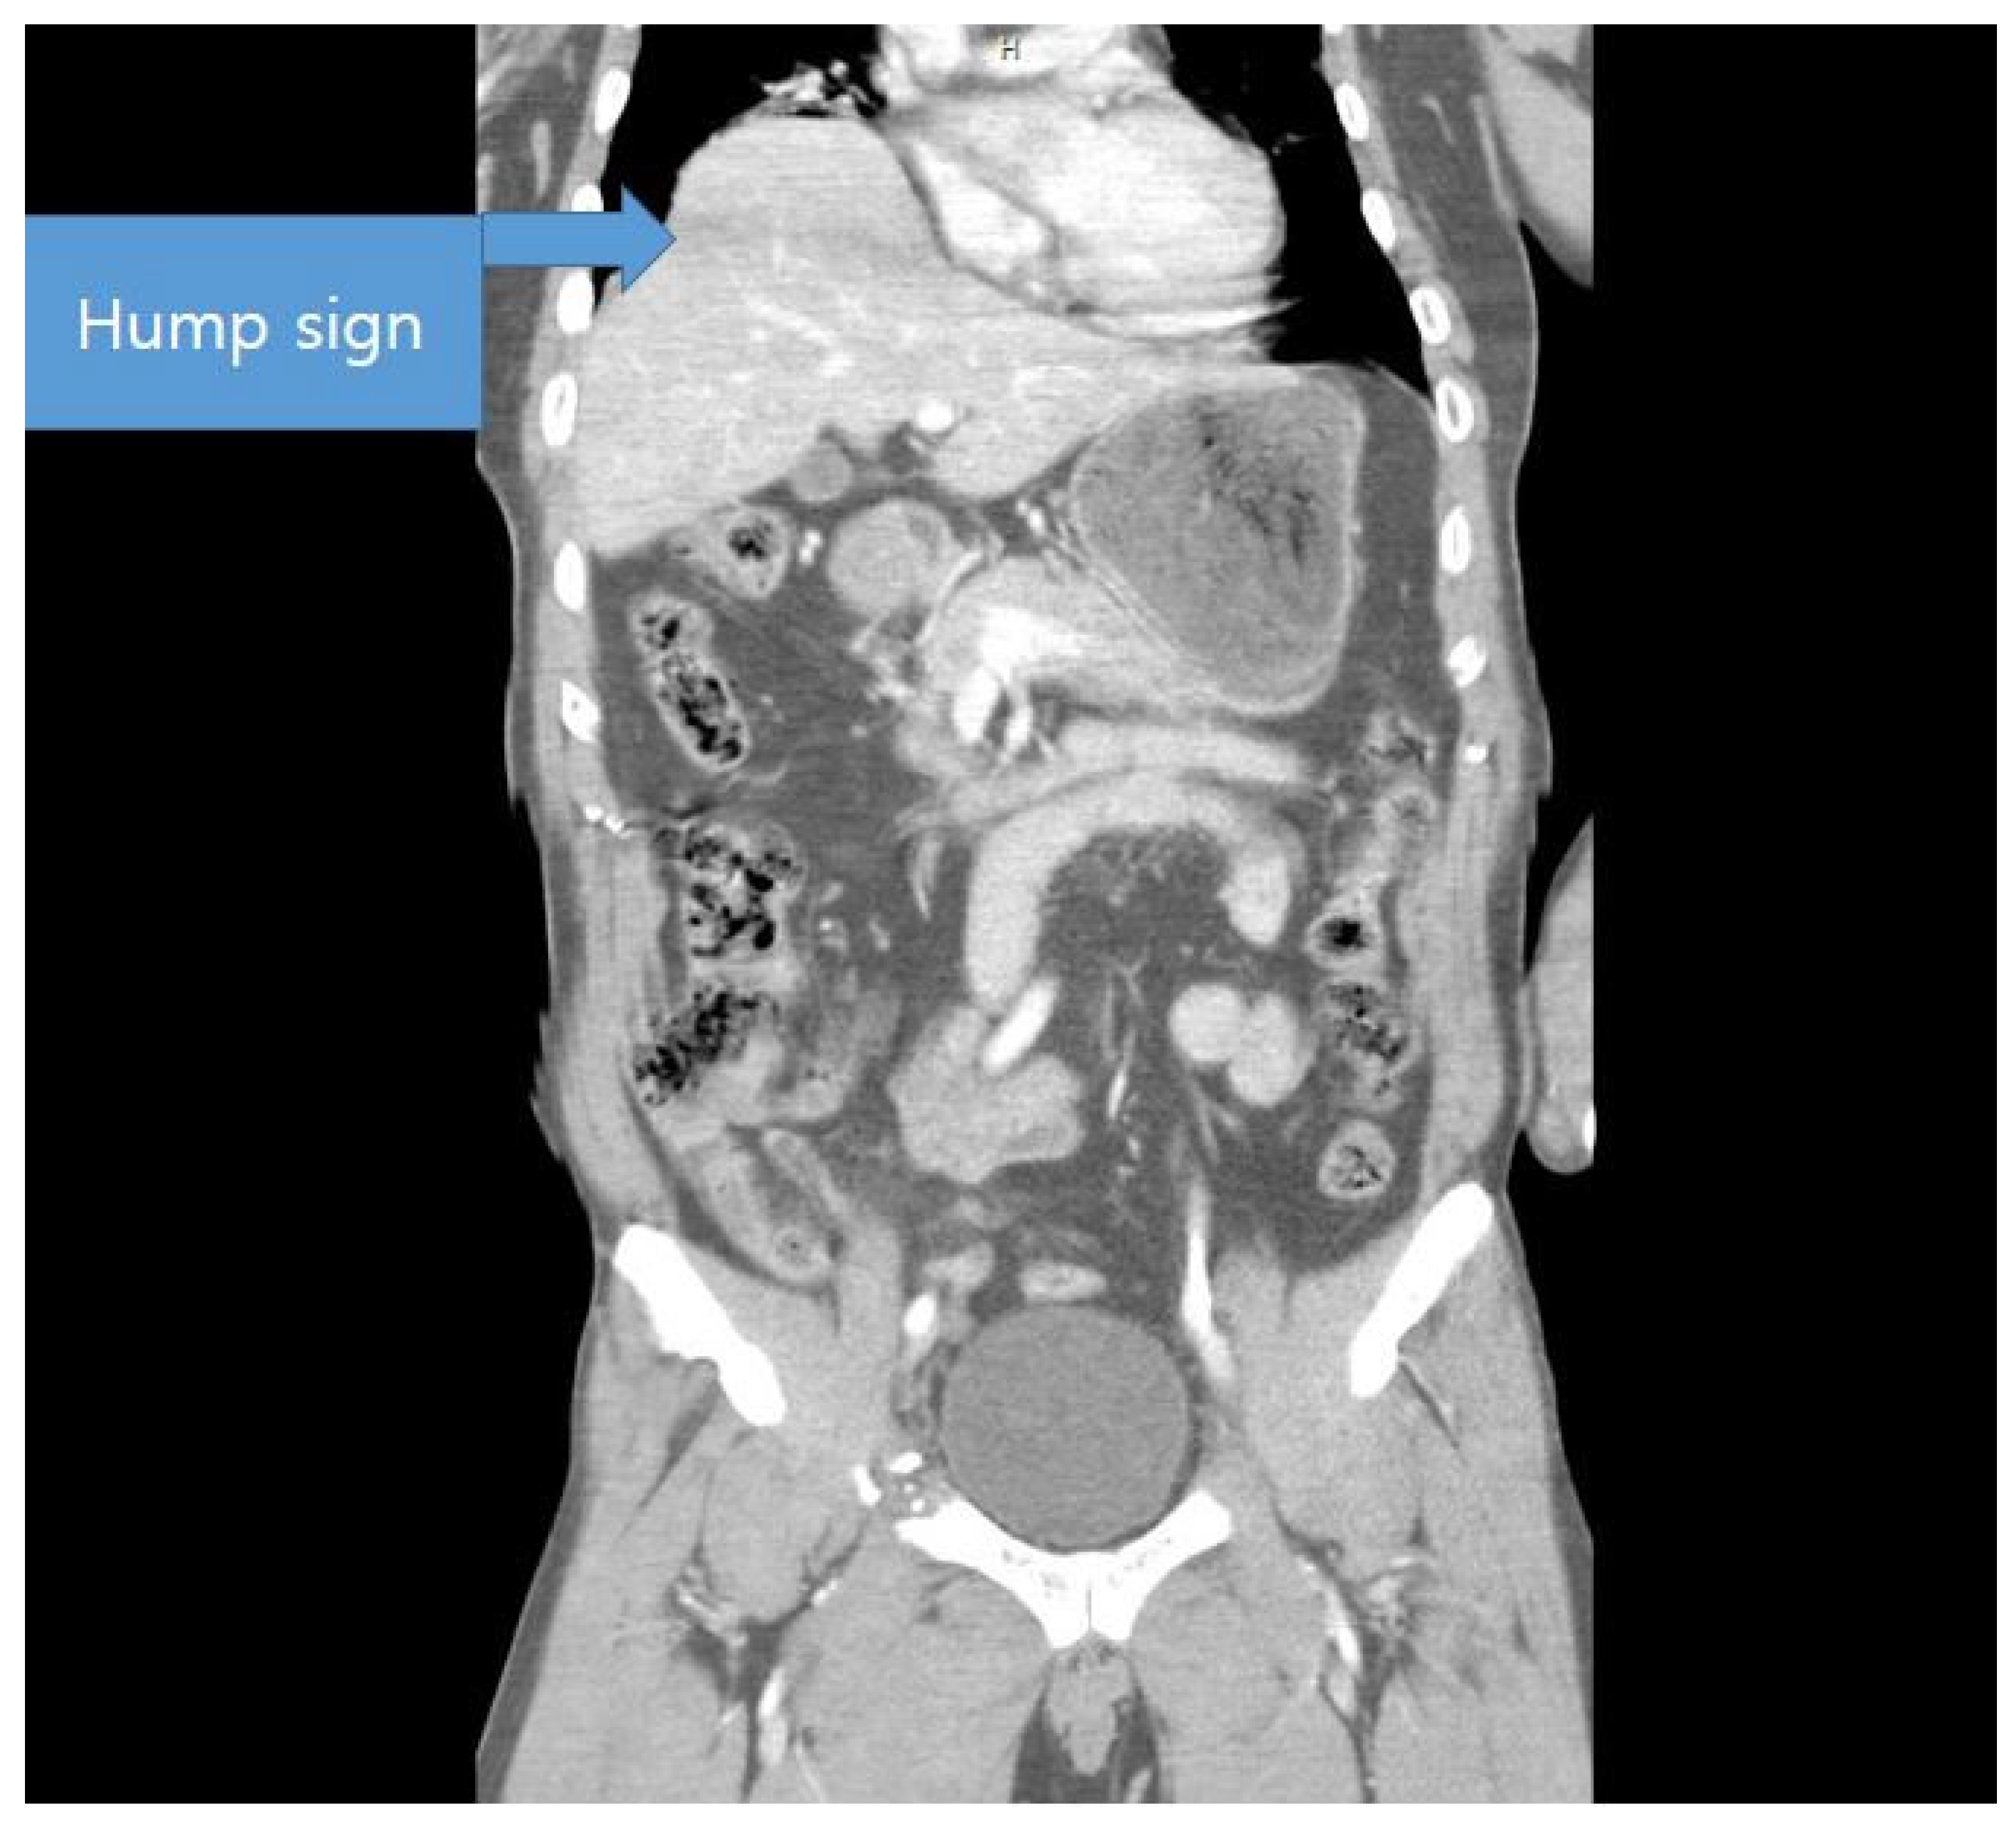

4.2. Diagnosis of Diaphragmatic Injury